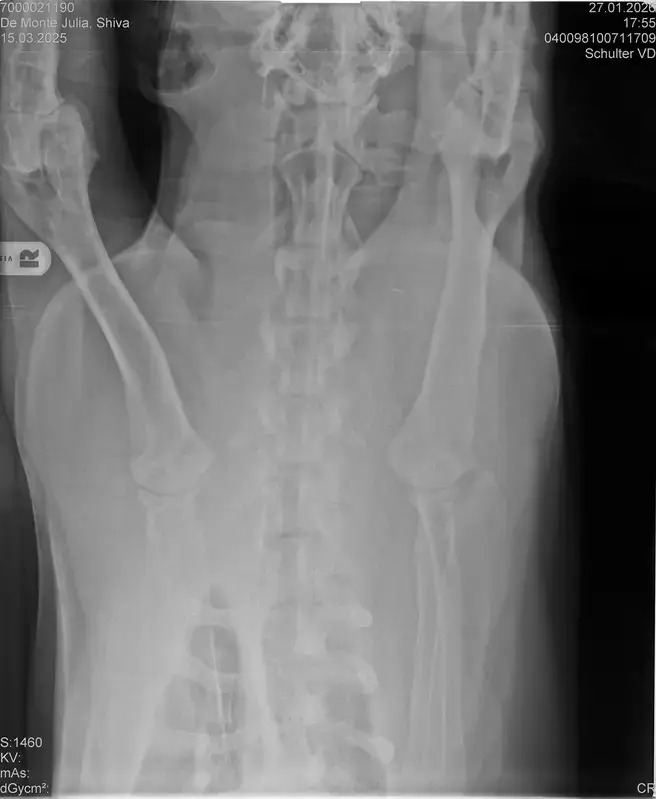

Vorige Woche kam mir Shiva verändert vor, nicht der aufgeweckte Spaßvogel der er sonst ist. Ich dacht vl ist er im Garten iwie blöd ausgerutscht weil unser gesamtes Grundstück über Wochen von einer dicken Eisschicht überzogen war. Er lag viel rum, zuviel da er doch zu den Wirbelwinden unter den Junghunden gehört. Er quetschte sich zum schlafen an mich ran, was auch untypisch für ihn ist. Er ist immer so „iiiii fass mich nicht an“. Ich nehms ihn nicht böse er ist nicht der große Kuschler :D Hat er wohl von mir :D :D aber er pickte nur an mir dran, ruhen ohne Körperkontakt war nicht möglich. Fand ich schön aber da ich wusste dass es nicht Shiva ist machte ich mir schon Sorgen… Am nächsten Tag wollte ich ihn bürsten alles war wie immer, er legte sich hin und sah mir zu wie ich einen Fellberg stapelte. Bei seinen Hinterpfoten hörte ich auf und dachte mir ich fühl mal vorsichtig.. Plötzlich knurrte er mich an vor Schreck weil ich damit überhaupt nicht gerechnet hatte zuckte ich reflexartig zurück (was lt Trainerin ein Fehler war)… Aber ich hab nicht mit einer derartigen Reaktion gerechnet, Shiva hatte schon 2 kleine Verletzungen die ich ohne Probleme verarzten konnte. Am nächsten Tag gings ab zum TA. Mit Maulkorb da ich nichts riskieren wollte. Nach der Untersuchung wo er auch mehrmals knurrte gings ab zum röntgen. Und das riss mir den Boden unter den Füßen weg. Dann die Aussage von der TA „ich weiß sie wollen einen gesunden jungen Hund aber das ist Shiva leider nicht“. Was jetzt? Er ist so ein aufgewecktes Kerlchen, absolute Lieblingsbeschäftigung ist Parcour. Er macht es so gern, ja auch UO und Suchspiele aber das leuchten in seinen Augen wenn wir Geräte machen :( (er macht noch keine schweren Geräte wie A Tafeln oder springen… Aber die seichten macht er mit absoluter Leidenschaft.. Ruhe halten über mehrere Monate… nur langsames gehen oder schnüffeln.. puh ich weiß nicht wie ich ihm verbieten soll zu rennen und zu toben… Vl habt ihr Tipps für mich. Im Anhang der Befund und ein paar Bilder vom kleinen Wirbelwind. <3

Ich lese da draus, dass der Hund in mindestens einem Ellenbogen nicht sauber ist, HD "noch zugelassen" oder "mittel" hat, nen' 1er LÜW UND vielleicht sogar OCD. Das wär ja wahnsinnig...

• Naja die Diagnose kommt von einem „Facharzt“, lt TA war ihrerseits alles i.O. Sie wollte noch sicher gehen und die Bilder zur weiteren Befundung einschicken und das kam dabei raus. Und der Therapievorschlag beläuft sich auf Ruhe, Ruhe und noch mehr Ruhe. Und einer Schmertherapie von Gabapentin 800mg 1/2 Tablette 2x tgl, Carprodyl 120mg 1 1/2 Tabletten 1x tgl und TamaCan CBD Tropfen 10-15 Tropfen 2x tgl. 1x in der Woche soll ich telefonisch Auskunft geben wie es Shiva geht. Das ganze mal für 14 Tage. Sie meinte noch sie hat viele Junghunde die ein Leben lang Schmerzmittel nehmem müssten. Die Röhrenknochenentzündung heilt in der Regel von selber der Rest gehört beobachtet… Ich weiß im Moment auch nocht so recht.. Er tut mir nur wahnsinnig leid mit sovielen Diagnosen und für mich war erstmal vorrangig ihn schmerzfrei zu bekommen. Das ist er inzwischen und versteht die Welt nicht mehr warum er nicht wie sonst spielen und arbeiten darf. Im Anhang noch Röntgenbilder falls sich jemand damit auskennt bzw Interesse hat..

• Ok, die Röntgenbilder sind aber auch extrem schlecht.

Ich denke aber, dass du für ein Gutachten von Tellhelm nochmal neu röntgen lassen musst, ich finde, dass das Bild der Hüfte (HD und LÜW wird da beurteilt) und die Draufsicht auf die Ellenbogen (nötig zur Beurteilung von ED) unterirdisch sind!